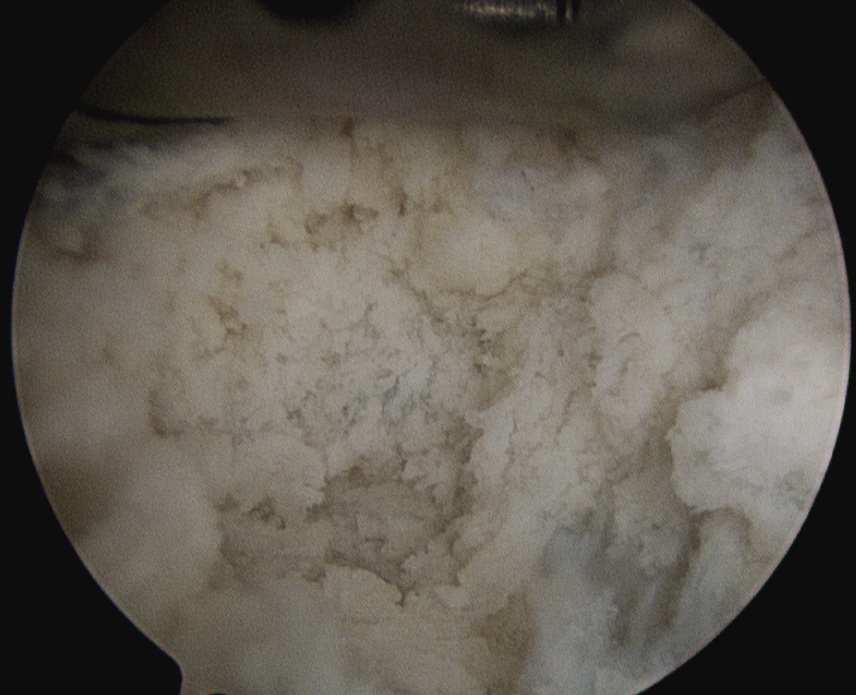

Calcium NoduleCalcium Needle

Location of calcium deposit under vision and with needle